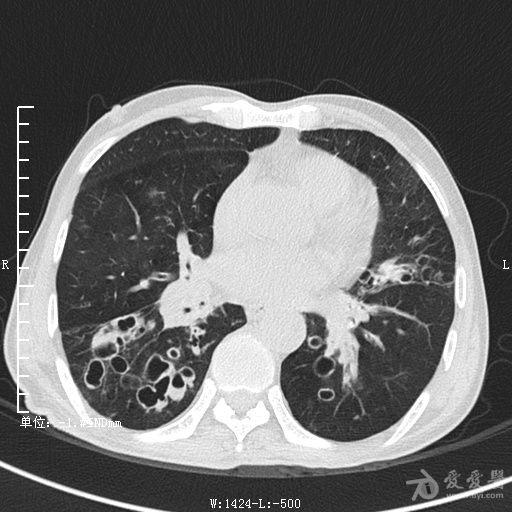

典型支气管扩张及肺水肿CT片

典型支气管扩张肺水肿